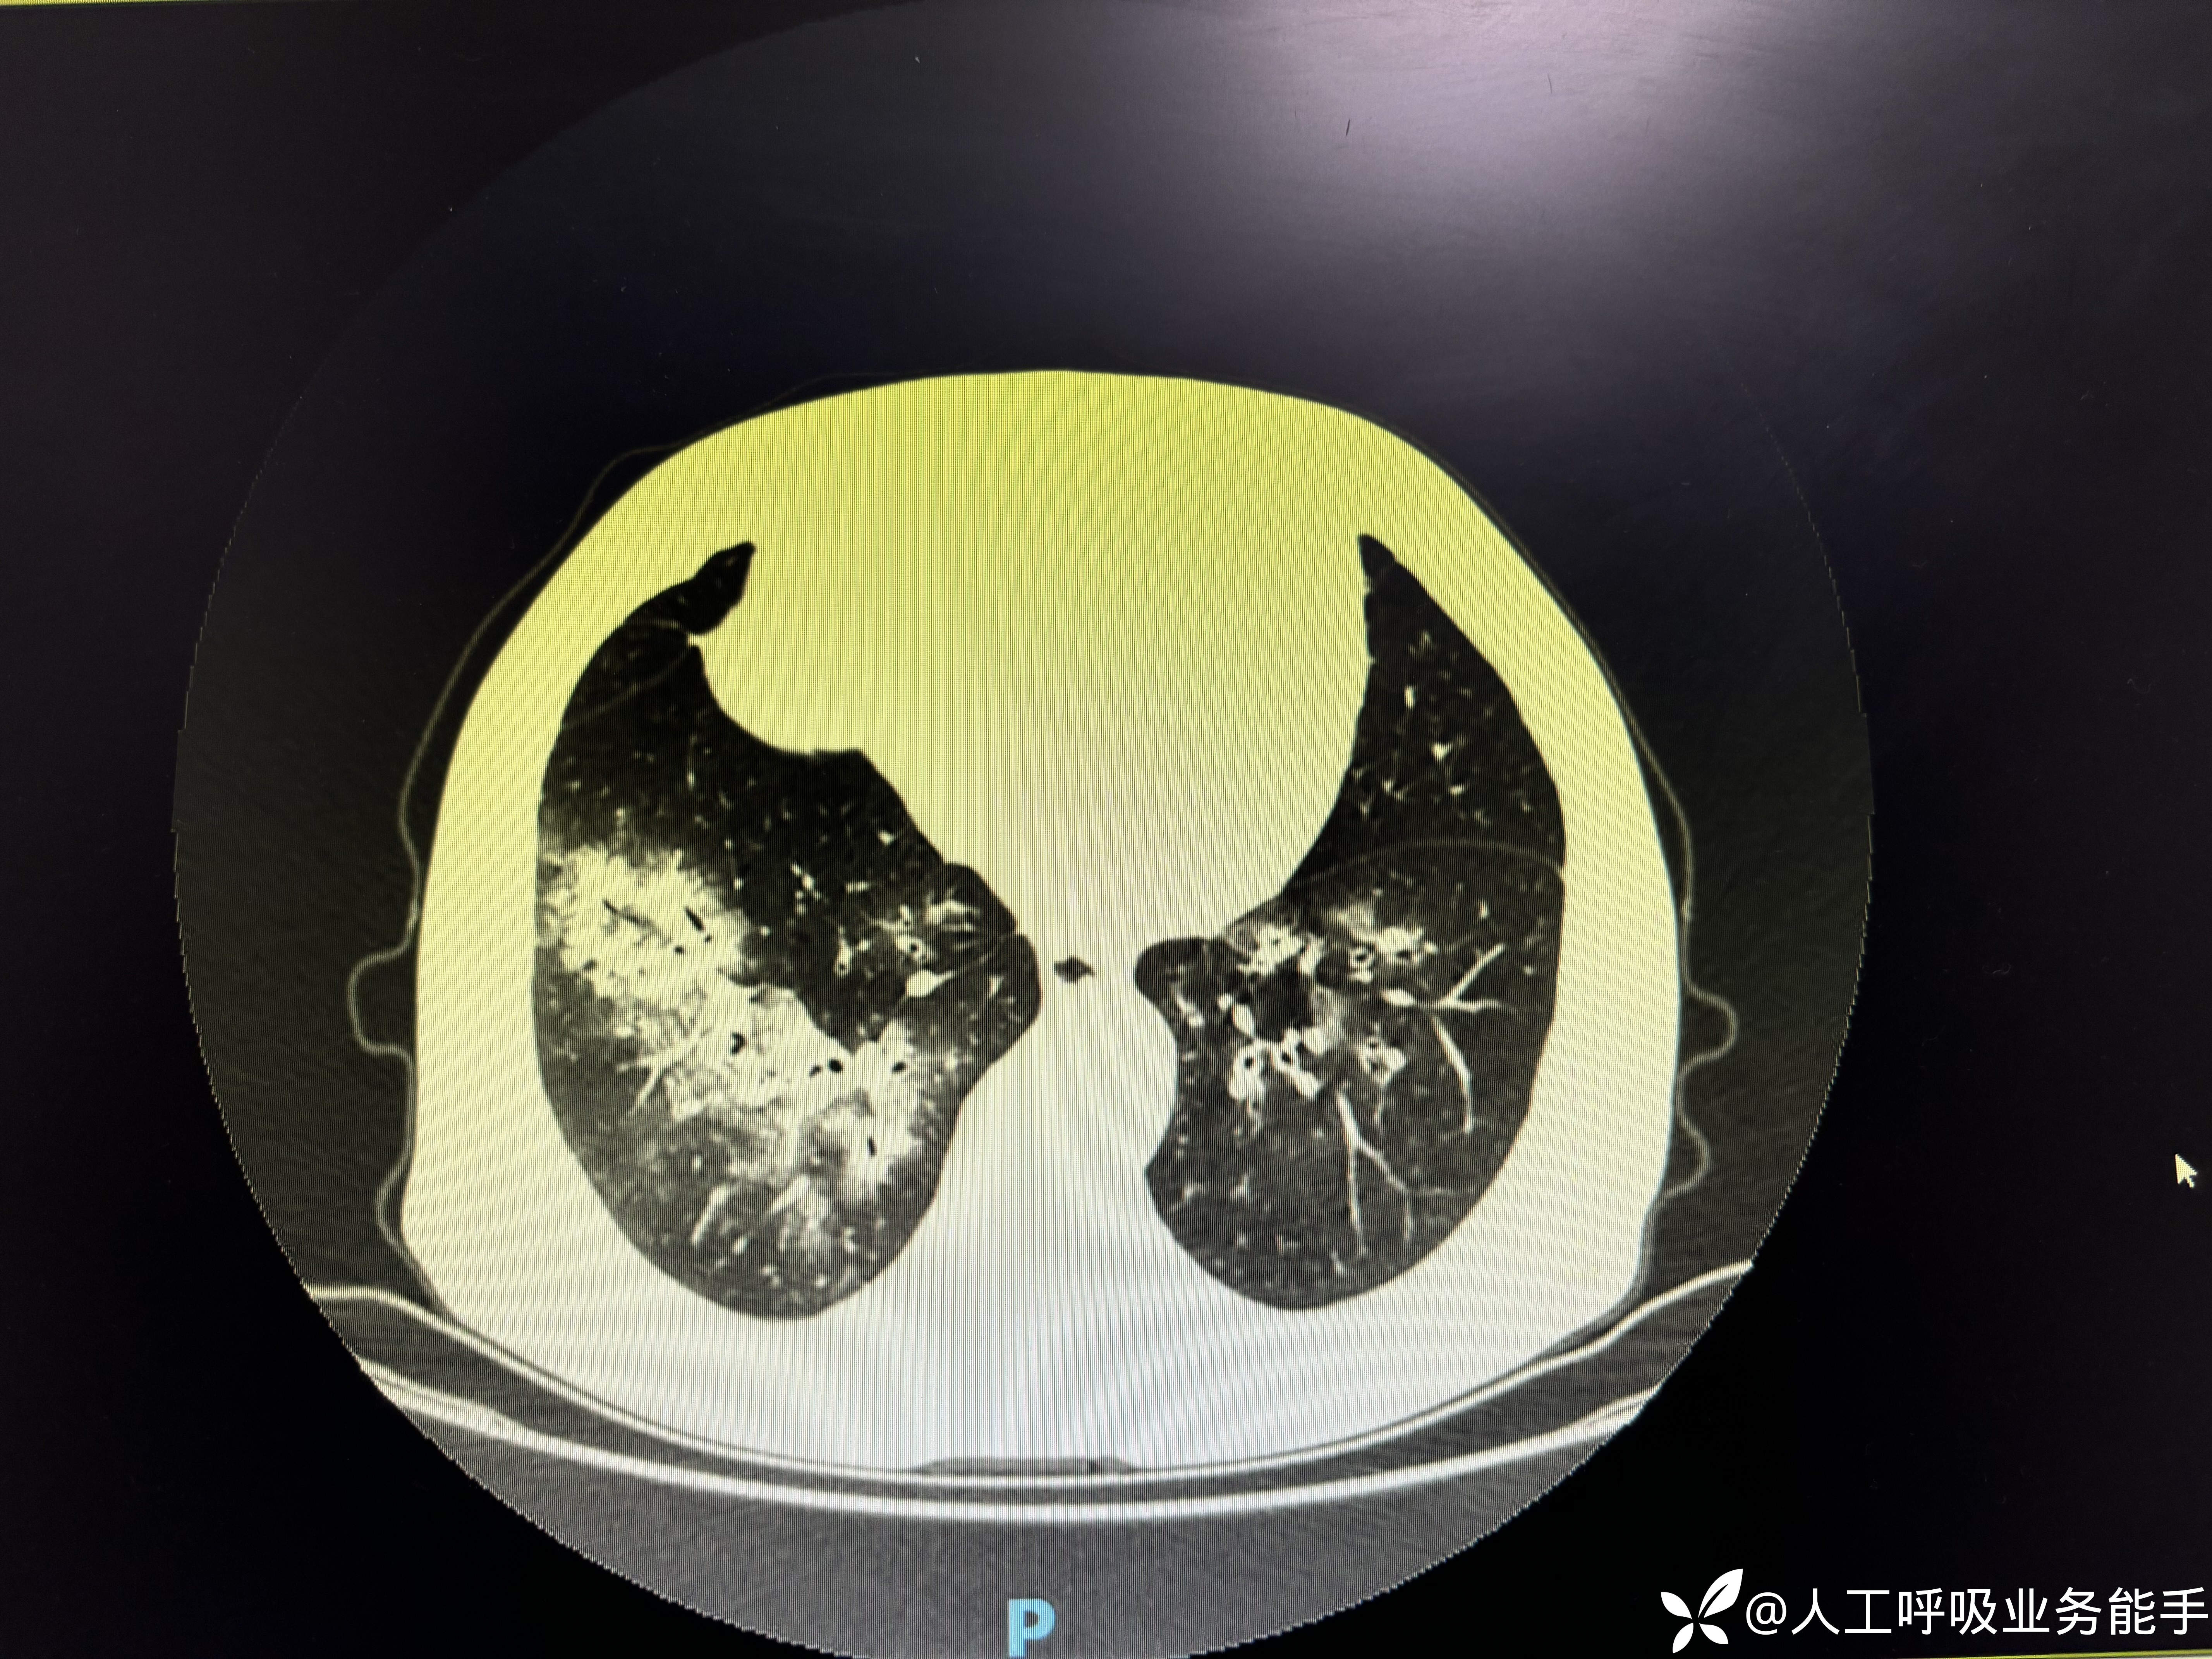

-1/26到我院急诊内科,血常规:WBC 10.71*109/L,CRP 111.6mg/L,Hb 128g/L,PLT 213*109/L,N 68% L 10% Eos 15%;尿常规:黄色清亮,蛋白质 1+,红细胞 2+,白细胞 -,复查胸部CT:

-胸部CT提示双肺多发病变,较前明显进展;